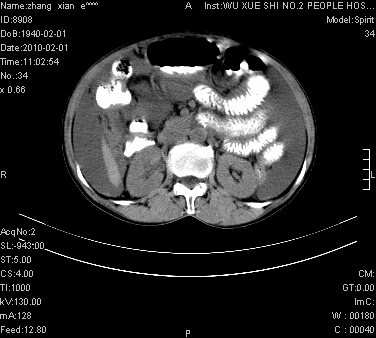

标题: CT24434:70岁 女 腹胀,腹水原因待查 [打印本页]

标题: CT24434:70岁 女 腹胀,腹水原因待查

大量腹水,脾脏囊性占位,子宫颈占位,右侧腹股沟淋巴结肿大,建议+c,先查妇科。

腹盆腔大量积液,子宫增大,子宫颈增大外形不规则,内见低密度影,膀胱后壁显示不清,右腹股沟肿大淋巴结,脾脏囊性占位,子宫颈占位,子宫颈癌?建议增强。

考虑:1、腹膜转移,大量腹水;

2、脾占位性病变;

3、左侧卵巢占位性病变,建议增强进一步检查。